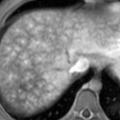

Syndrome de Budd-Chiari

Le syndrome de Budd-Chiari (SBC) est une affection rare caractérisée par une obstruction du drainage veineux hépatique, commençant au niveau des veinules hépatiques jusqu’à la partie terminale de la veine cave inférieure. Il peut se manifester par un tableau d’hépatite fulminante, notamment en cas d’obstruction complète des trois…